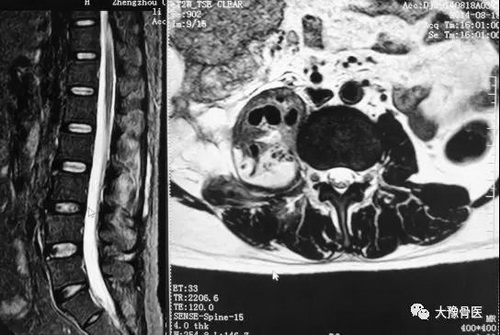

病例七:女性,69岁,以“腰痛20天”来诊,在当地医院按“腰椎间盘突出症”给予治疗,症状无改善,遂来我科就诊,后确诊为腰柱结核,硬膜外及腰大肌脓肿。